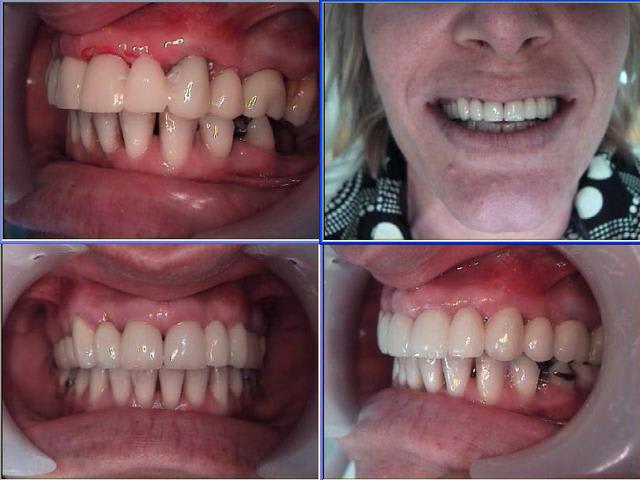

bridge fait en 2007. Avec la supra et le sourire gingival, je décide de faire une élongation coronaire esthétique de 11 21, et donc de les couronner ensuite. on aurait pu mettre deux implants en 12 et 22, et ne pas toucher aux centrales, mais je pense que le résultat final n'aurait pas été le même.

Photo : état initial, puis après chir ( élongation 11 21, greffe conjonctif 23 ), un mois après , rv de 3 heures et pose du provisoire maison, résultat final. je l'ai revu il y a 15 jours, je n'ai pas fait de photo, mais tu peux me croire, cela n'a pas bougé d'un poil.